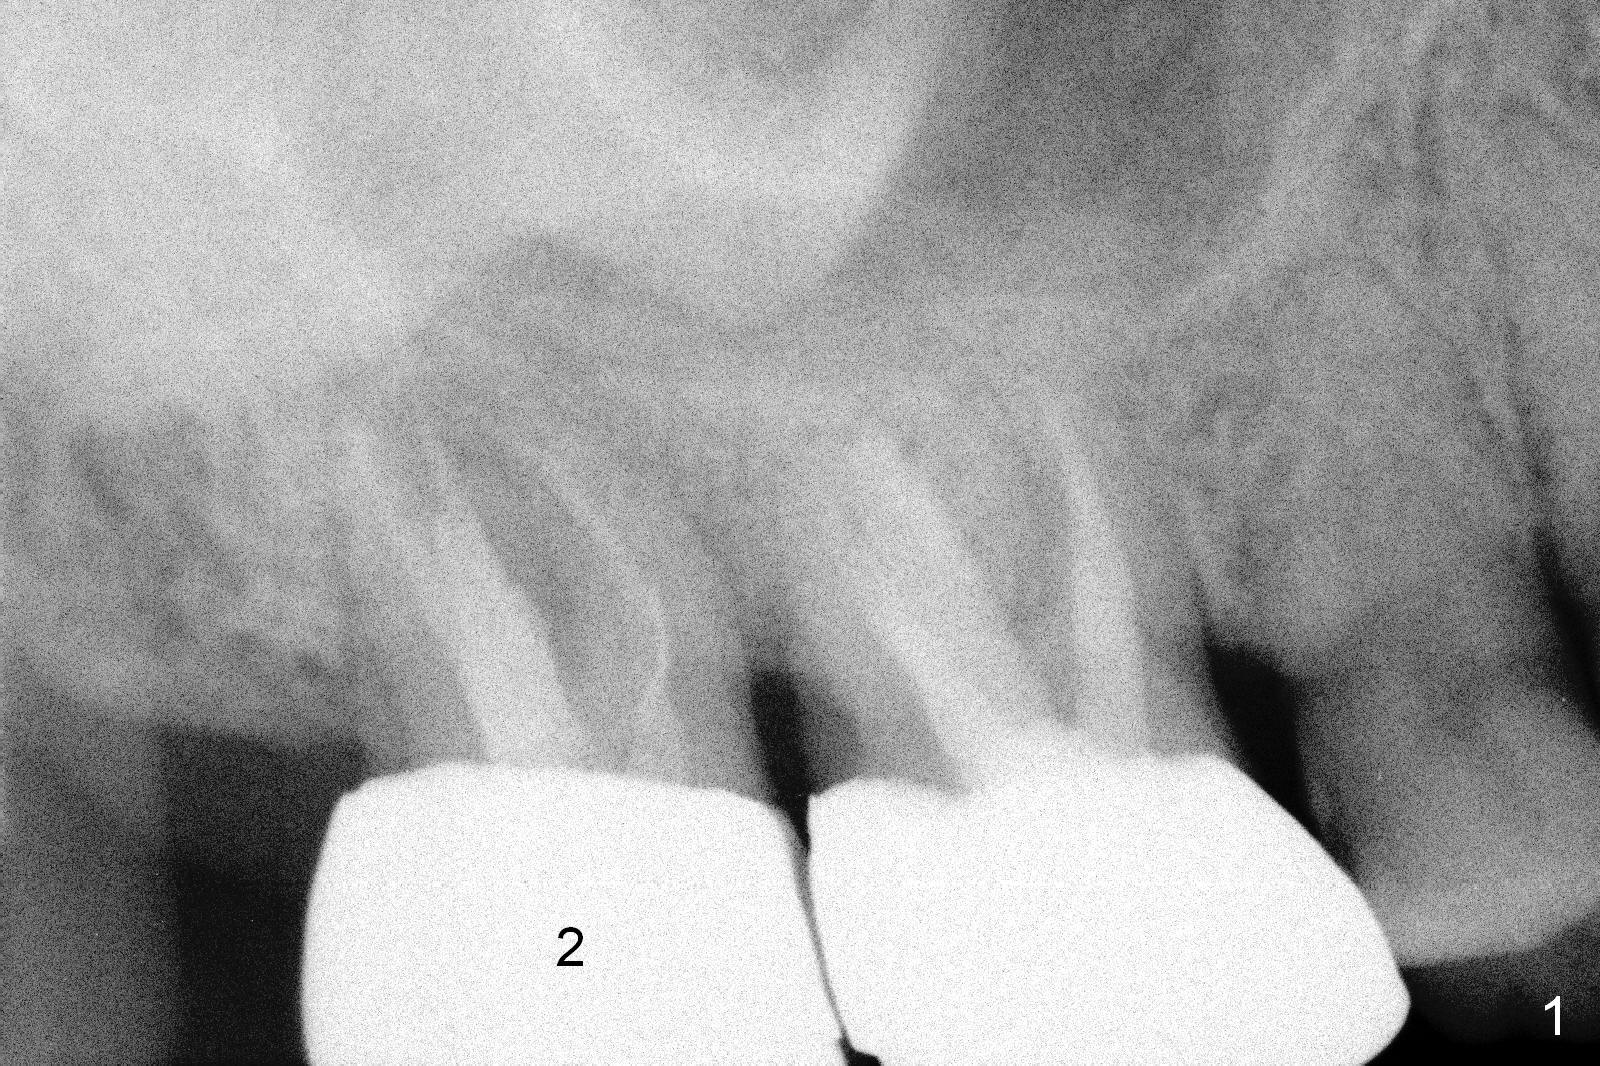

A 59-year-old man is a bruxer, fracturing the teeth #8 and 9. Now the tooth #2 seems to have fractured (Fig.1). Since the apices appear to protrude into the sinus, either 7x14 mm tissue-level (Fig.2) or 6.9x10 mm bone-level (Fig.3) implant will most likely penetrate the sinus floor (red dashed line). To protect the sinus membrane, PRF membrane or plug (blue curved line) is to be placed prior to bone graft (yellow circles) and implant placement. Prepare Magic Expanders and Magic Sinus Lifter. Clindamycin will be used after extraction. Since the roots of the upper 2nd molar usually fuse, prepare large gauzes for hemostasis. Check the buccal and palatal walls for any defect. Start osteotomy away from the defective wall. Place the remaining PRF membrane for wall repair before bone graft. Set stopper 2 mm short of the intended bone-level implant length.